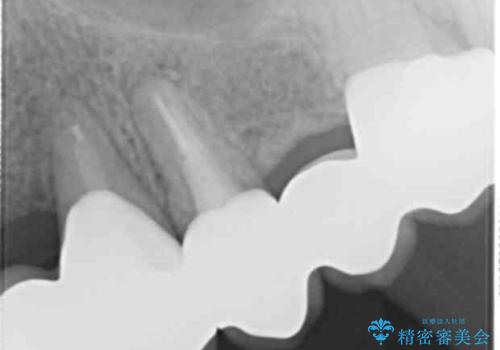

犬歯は歯ぐきの奥深くまで割れており保存不可能な状態でしたが、どうしても抜きたくないとのことでした。

歯を牽引し健全歯質を歯肉縁上まで引き上げ、歯の保存を試みることにしました。

根の長さが短くなるためブリッジの支台歯としては弱いこと、長期的予後は不明なことをご理解頂いた上で治療を行いました。

健全歯質を歯肉縁上に出すためにしっかり挺出させたことで歯根長が短くなりましたが、仮歯で十分に保定した結果動揺度Ⅰ程度となり、ブリッジの支台歯にすることが可能と判断しました。